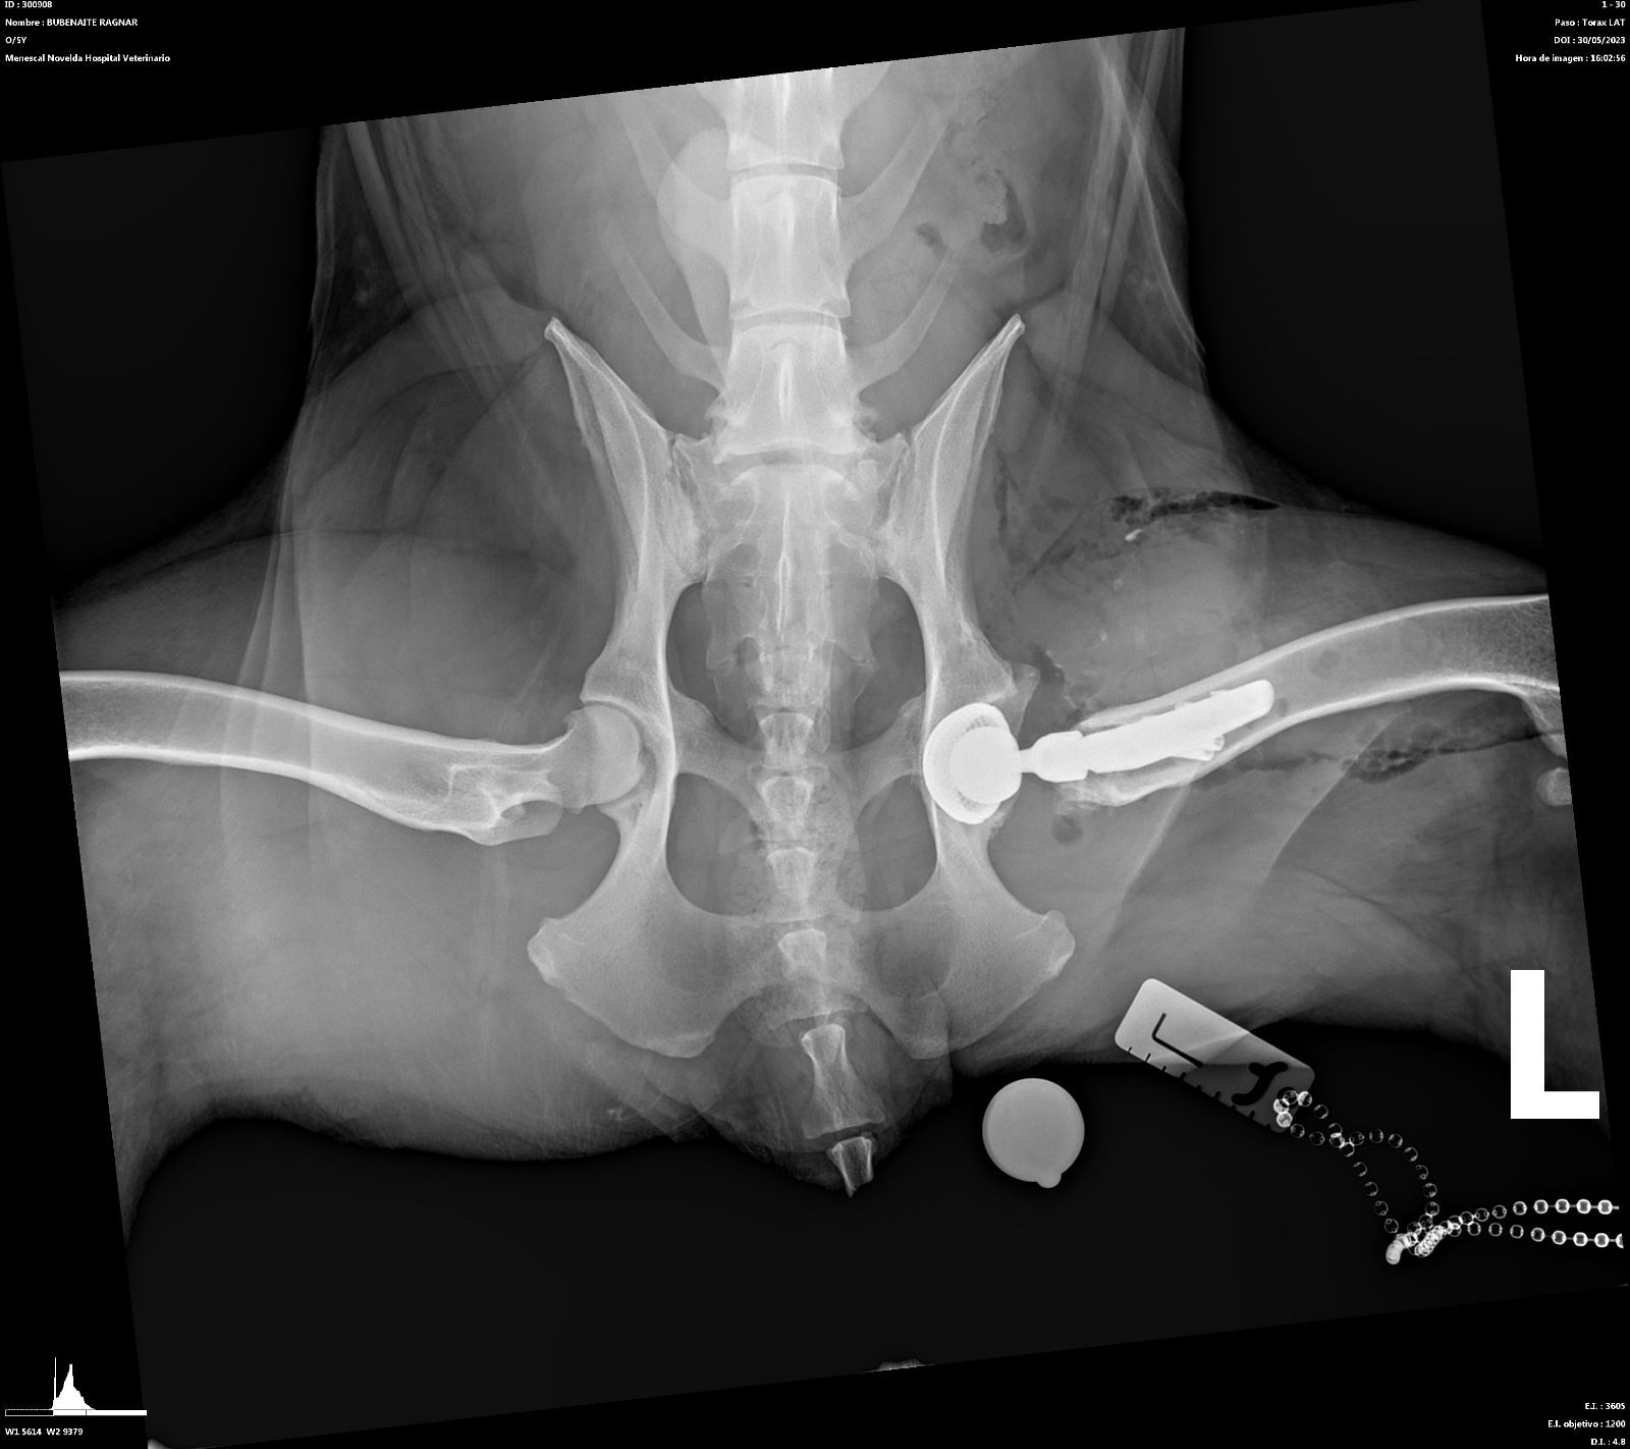

El diagnóstico de la displasia de cadera generalmente se alcanza a través de un completo examen ortopédico y con la realización de un estudio radiológico de las caderas bajo sedación o anestesia general. En este último los hallazgos pueden ser variables, desde incongruencia articular, hasta presencia de signos de degeneración articular (artrosis) como puede ser la deformidad coxofemoral y la aparición de osteofitosis (depósitos anormales de hueso) en la articulación.

- Prótesis de cadera: es una técnica que generalmente se indica en pacientes adultos que padecen una enfermedad degenerativa articular (artrosis) avanzada. Consiste en la sustitución de los componentes acetabular y femoral afectados e involucrados en la articulación, por unos sintéticos, que permitirán una movilidad apropiada y sin dolor. Aunque es muy posible que un paciente necesite una prótesis en ambas caderas, nunca se realizarán de forma simultánea, espaciando las mismas el tiempo necesario para asegurar la recuperación de la primera. La mayoría de perros se encuentran bastante confortables pocos días después de la cirugía y vuelven a alcanzar niveles de actividad elevados unos meses más tarde.